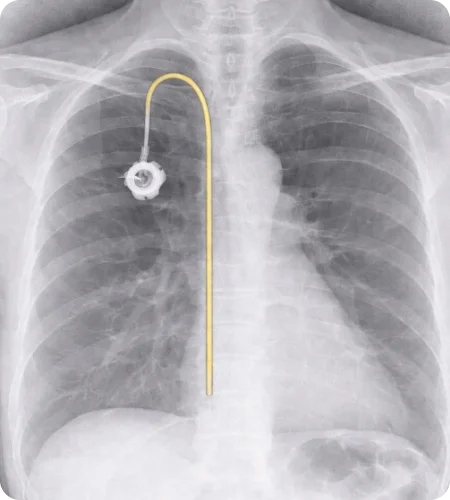

Port-a-cath

Insertion

A Port-a-Cath is a small medical device placed under the skin to provide reliable long-term venous access for treatments such as chemotherapy, medications, or blood tests. Image-guided placement ensures accurate positioning and patient comfort.